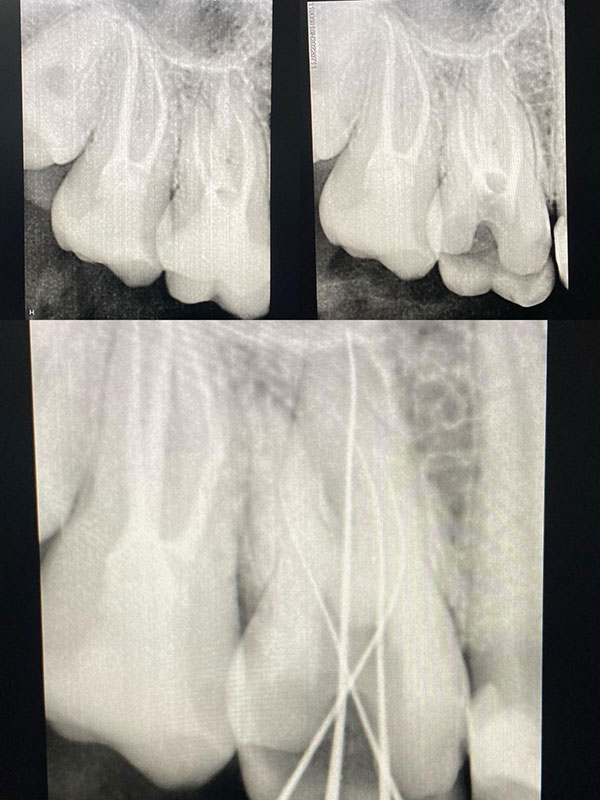

Општата стоматологија се грижи за севкупната хигиена и здравје на усната празнина. Таа ги опфаќа редовните прегледи, професионалното чистење, дијагностиката на рани симптоми и третманите кои спречуваат развој на посериозни состојби. Во фокусот е индивидуализираниот пристап кон секој пациент, бидејќи превенцијата е најдоброто лекување.

Реставративната стоматологија, пак, се надоврзува како уметност на враќање. Со користење на најсовремени материјали и технологии, се реконструираат оштетените или изгубените заби – без компромис во однос на природниот изглед, функцијата или удобноста. Без разлика дали станува збор за пломби, инлеи, коронки, мостови или импланти, секој реставративен зафат е прецизно дизајниран да се вклопи во хармонијата на вашата насмевка.